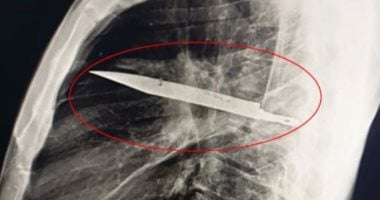

تباشر النيابة العامة فى أكتوبر تحقيقاتها في واقعة اعتداء سيدة على زوجها باستخدام سلاح أبيض "سكين" بمدينة 6 أكتوبر، ما أسفر عن إصابته، وذلك للوقوف على ملابسات الواقعة وأسبابها.

وكانت الأجهزة الأمنية بمديرية أمن الجيزة قد تلقت بلاغًا يفيد بإصابة عامل بطعنة بسلاح أبيض داخل نطاق مدينة 6 أكتوبر، وعلى الفور جرى نقله إلى المستشفى لتلقي الإسعافات اللازمة.

وكشفت تحريات رجال المباحث أن زوجة المجني عليه هي مرتكبة الواقعة، حيث اعتدت عليه إثر خلافات أسرية سابقة بينهما، وذكرت التحريات أن المتهمة كانت قد تركت مسكن الزوجية منذ عدة أيام قبل وقوع الحادث.

وعقب تقنين الإجراءات، تمكنت الأجهزة الأمنية من ضبط المتهمة، وبمواجهتها أقرت بارتكاب الواقعة، فتم اتخاذ الإجراءات القانونية اللازمة حيالها